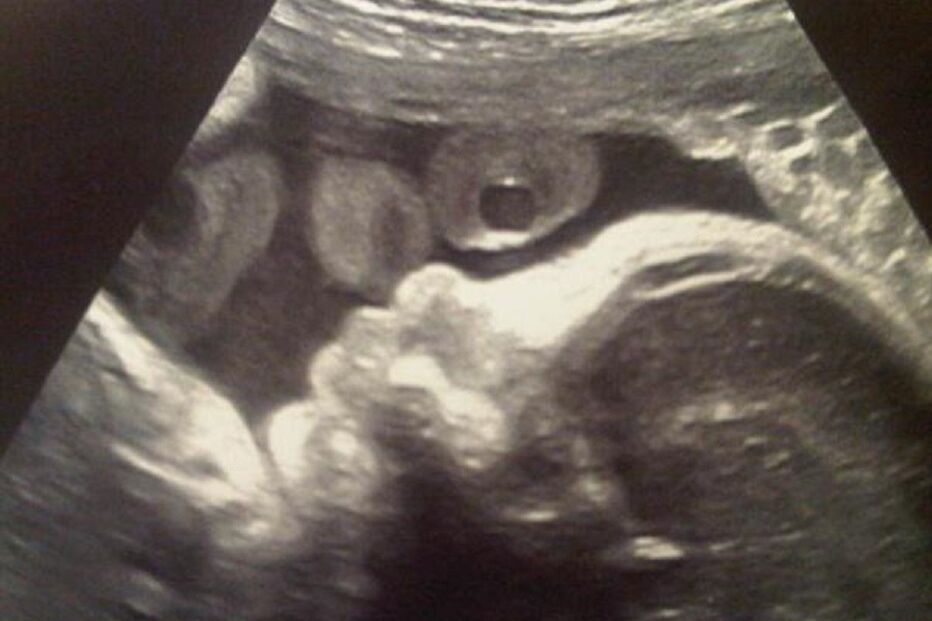

O Governo chinês lançou uma campanha contra os abortos em função do sexo do feto de forma a reduzir o desequilíbrio na proporção entre homens e mulheres, informou hoje a agência oficial Xinhua.

Segundo a mesma fonte, um dos objetivos da iniciativa, que a Comissão Nacional de Saúde e Planificação Familiar pôs em marcha em abril e que se prolonga até novembro, é diminuir a recorrência das mulheres a exames médicos que determinam o sexo do feto.

Os abortos em função do sexo do feto, um fenómeno social conhecido como feticídio, e os exames que o determinam são ilegais na China, embora a preferência por filhos varões e a política do filho único (instaurada no final da década de setenta e que foi revista no final de 2013) tenham tornado estas práticas populares.